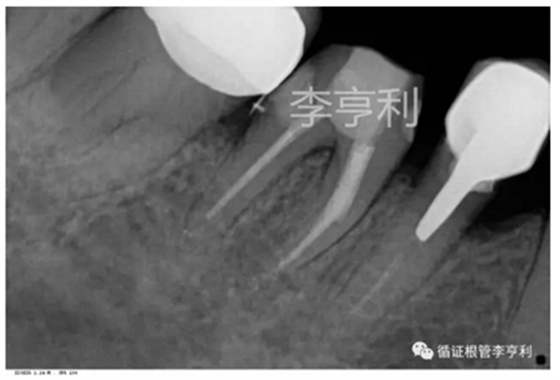

試尖片 (2017-07-03)

術后片 (2017-07-03)

分離器械約為4mm長 (2017-06-26)

【治療過程】:由于患者根管系統(tǒng)較細窄,無法建立旁路疏通MB根,因此決定取出分離的器械。首先在顯微鏡下暴露器械斷端,然后使用超聲工作尖震動斷針,30分鐘內(nèi)斷針被順利震出,然后疏通MB到根尖。之后就常規(guī)完成剩余根管治療步驟,轉回進行后續(xù)冠修復。